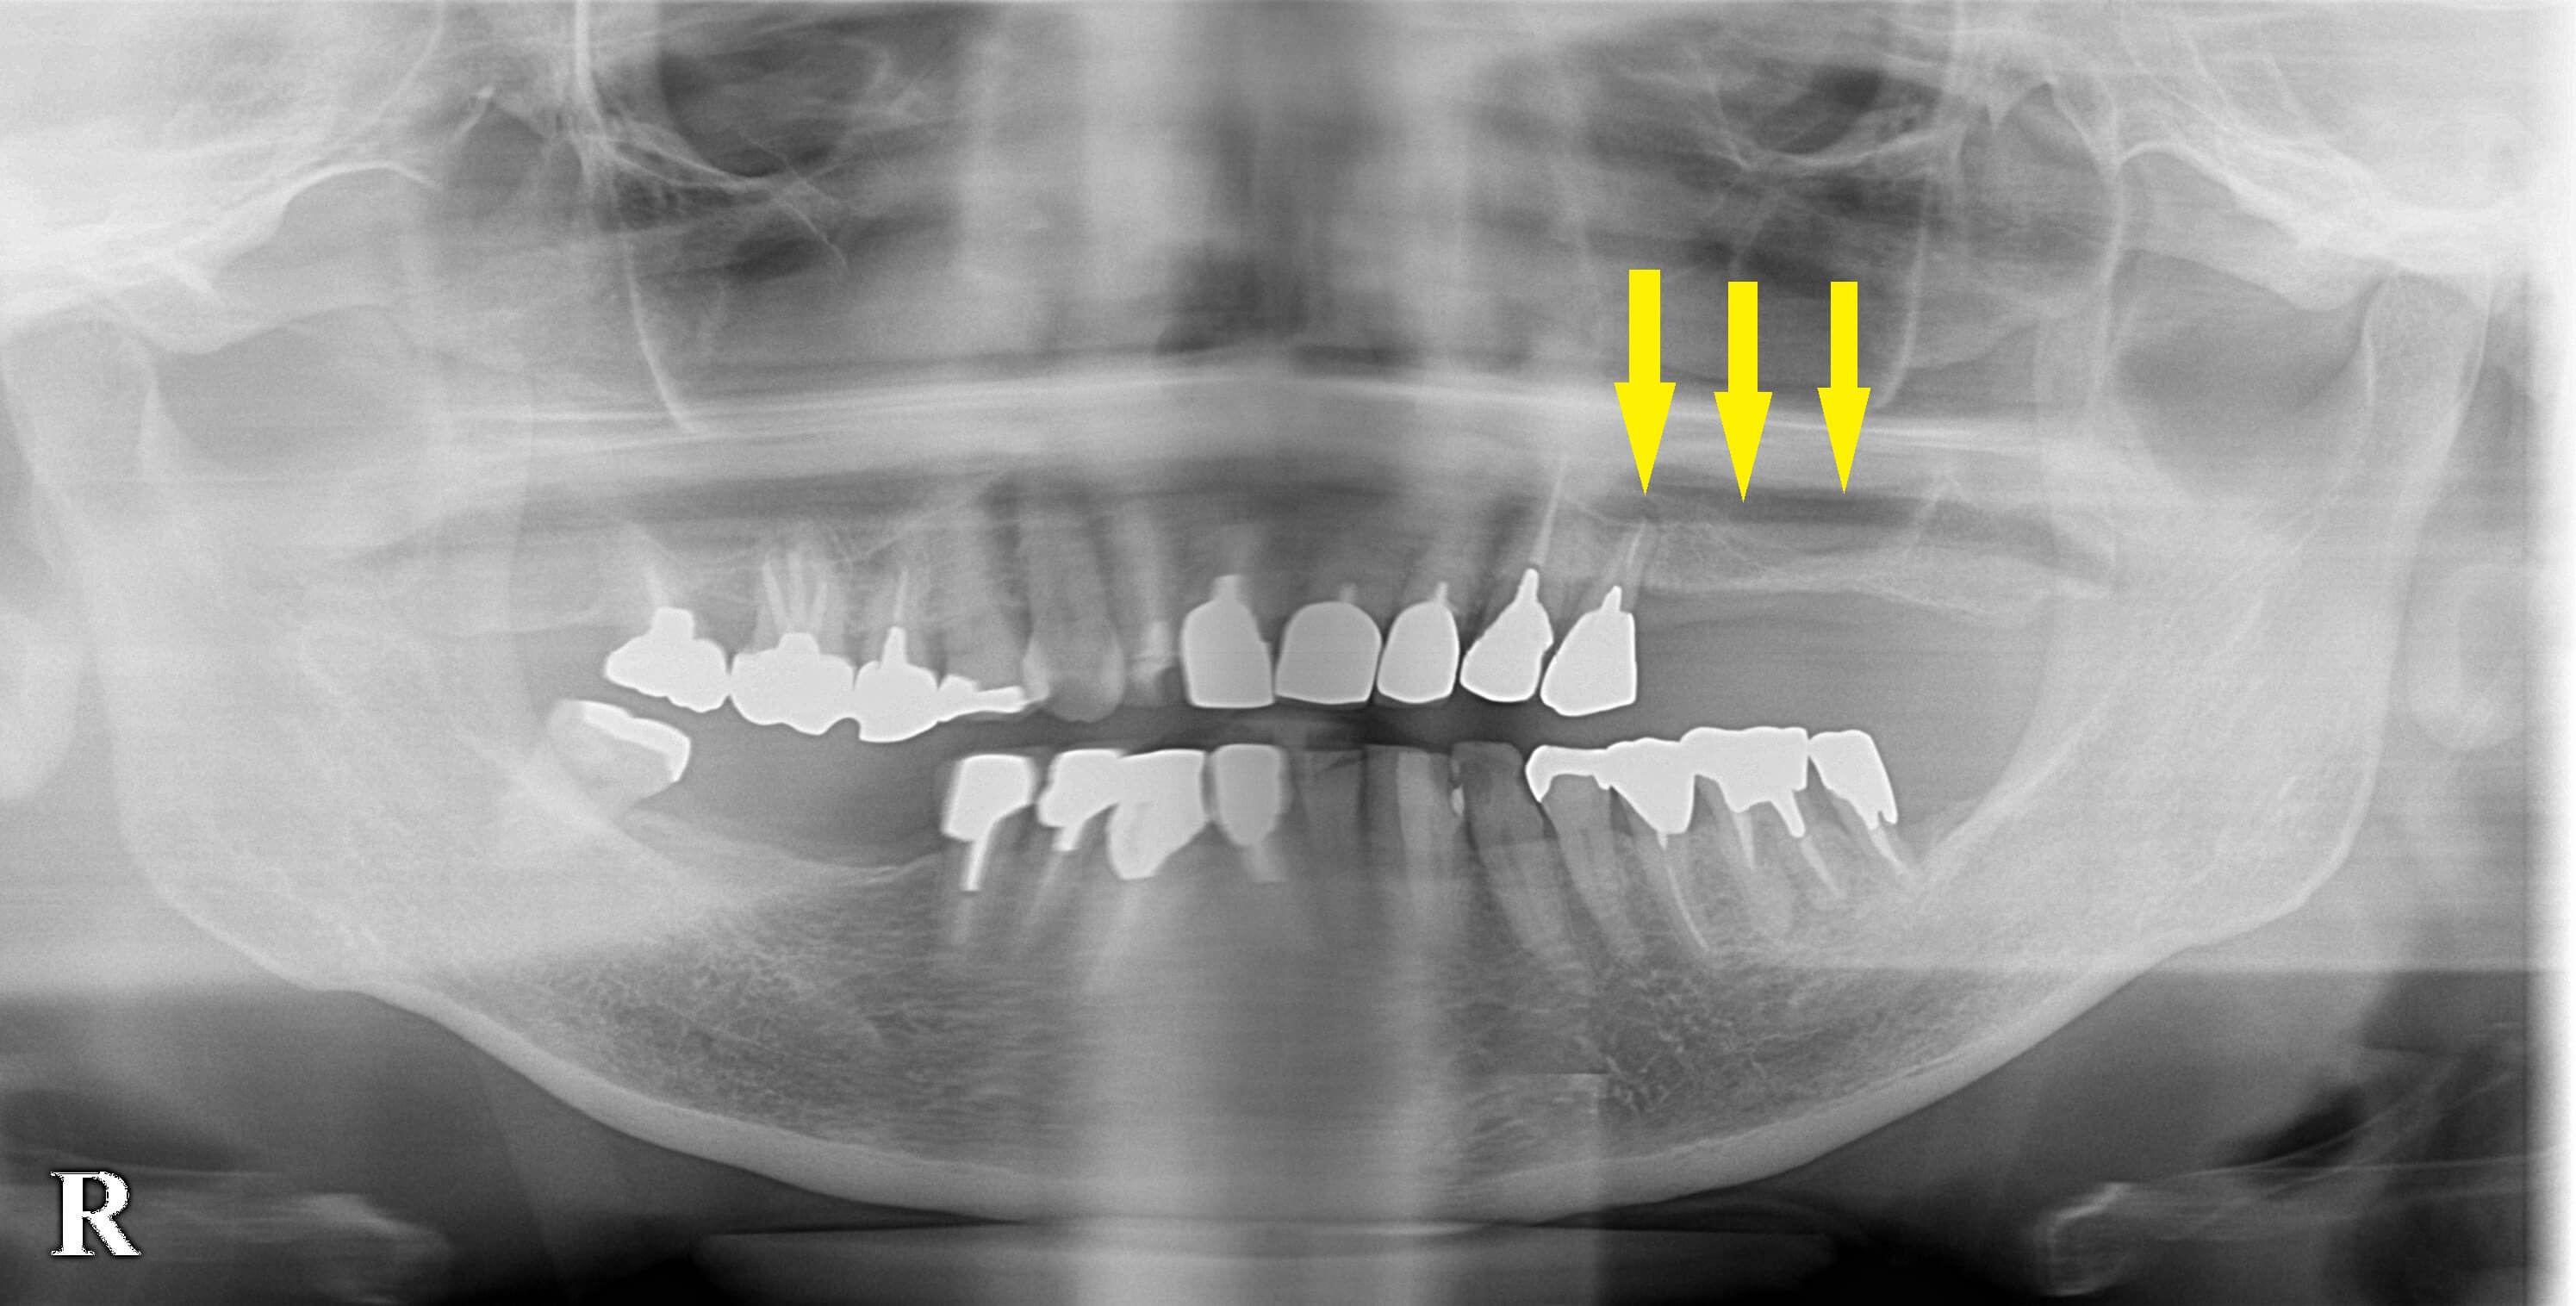

左上顎に残った小臼歯は、歯根を支える歯槽骨が、大きく吸収され、骨の吸収は上方の空洞まで達していました。

抜歯後、CTを撮影してみると、大きな穴が空いた状態で、インプラントの埋入はかなり困難な状況でした。

この歯の部位を含め、その後方の骨の薄い部分まで、人工骨で骨造成を行いインプラント埋入を目指します。